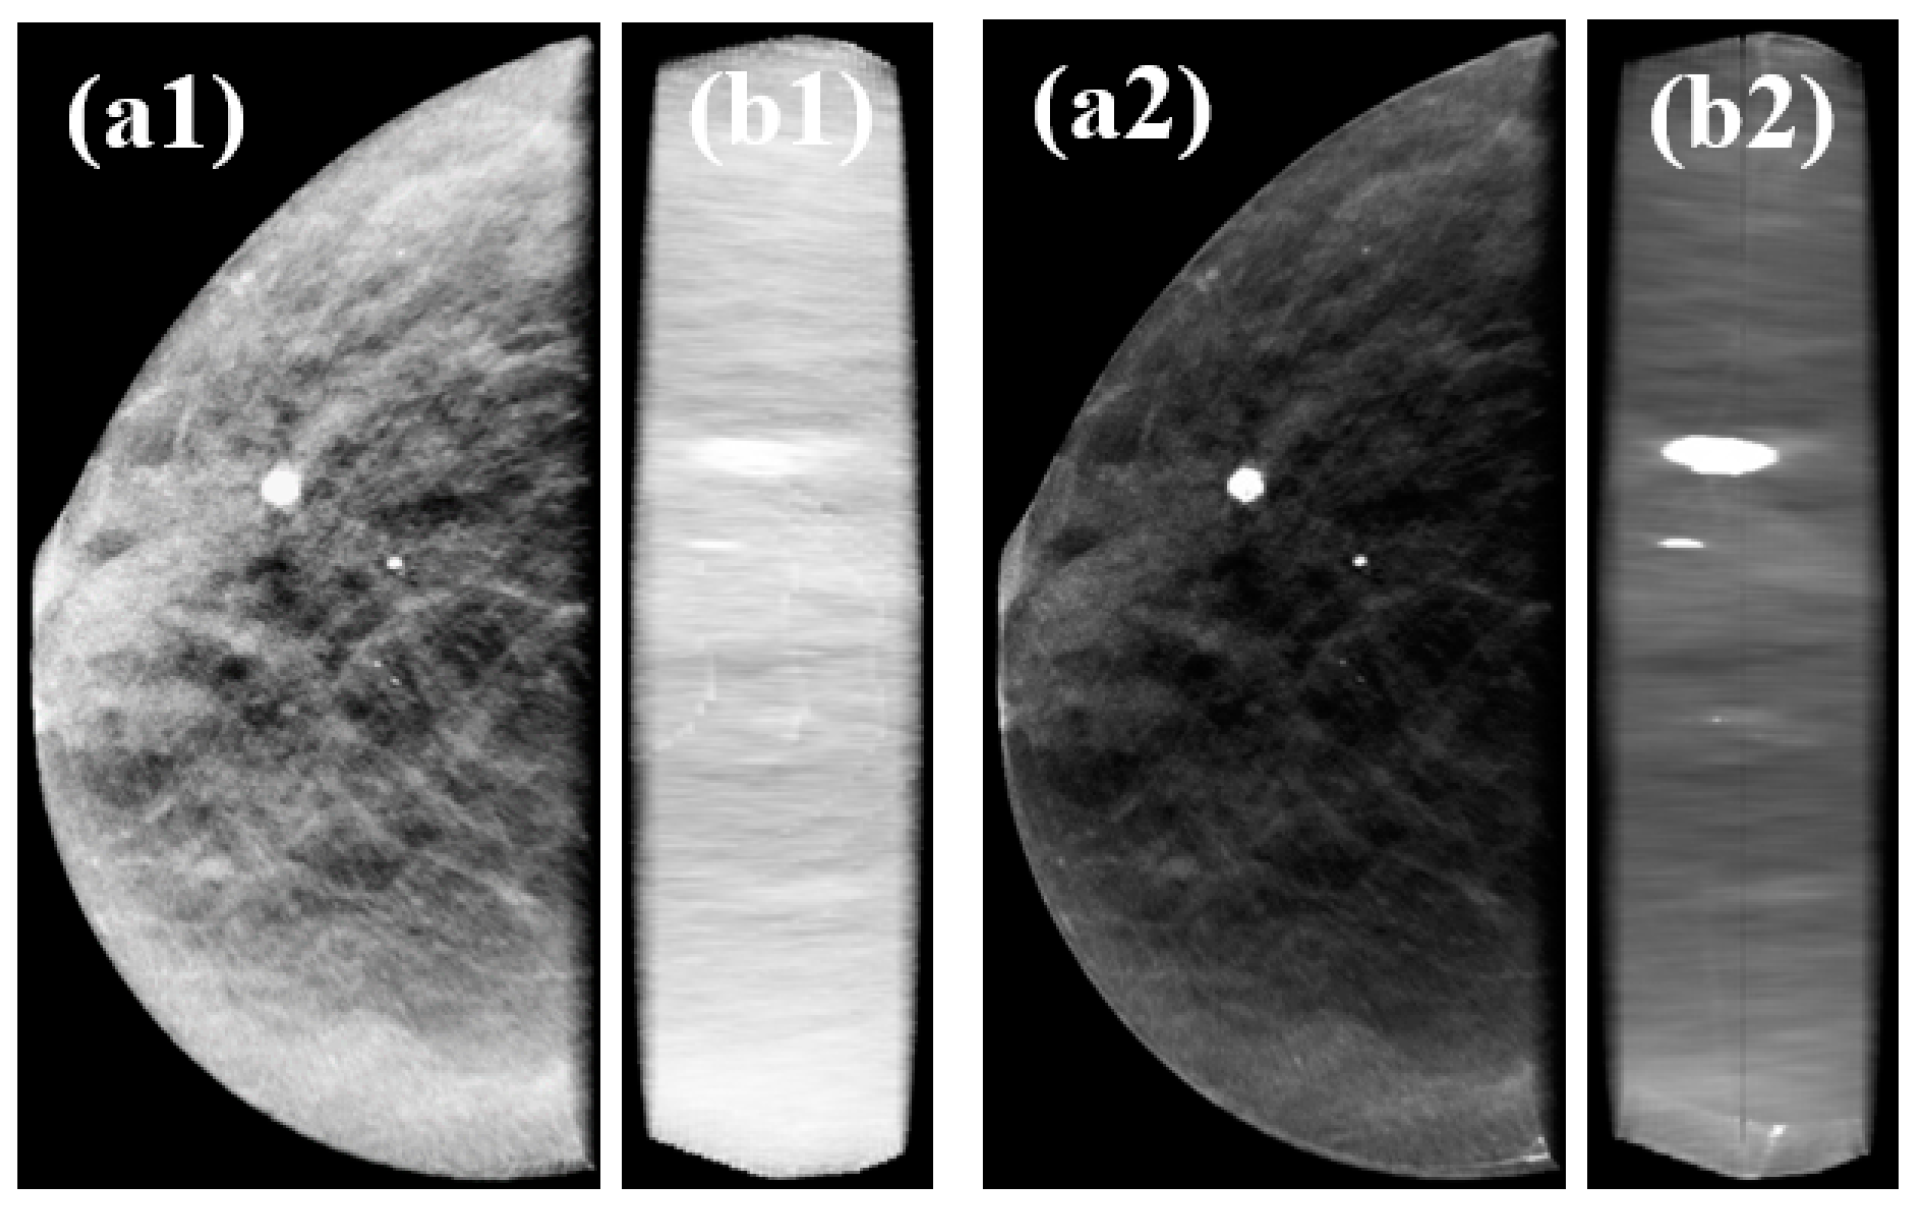

3.4. Clinical Data